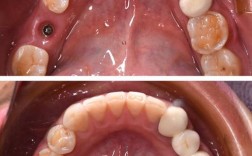

- 种植位置(如上颌左侧第一磨牙)。